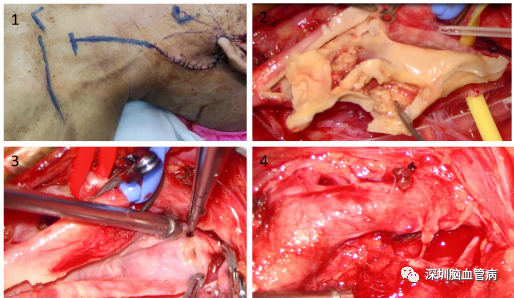

图2 腮腺肿物切除术

图3 在原切口的基础上适当延长,行颈动脉内膜剥脱术。

术中,首先由苗北平主任进行腮腺肿瘤切除,探查发现腮腺内一个表面光滑,质地较韧、包膜完整新生物,达腮腺深叶,内含囊液,约4cm*2cm*2cm大小,肿物与周围腮腺组织无明显粘连,予以完整切除,术中送病理提示腺淋巴瘤。紧接着,伍健明主任团队在原切口的基础上进行颈动脉内膜剥脱术,显微镜下暴露颈动脉分叉处,临时阻断动脉远端和近端,切开颈动脉后见斑块累及颈内、外动脉,颈总动脉,仔细剥离切除斑块后缝合动脉壁,随后B超探查血管通畅无斑块。整个手术过程,两个团队密切配合,在确保患者生命安全的前提下,同时治疗了颈动脉狭窄和腮腺肿瘤,减少了患者二次手术的痛苦,同时也减轻了经济负担。术后经过精心的治疗和护理,患者恢复良好,没有出现面瘫、肢体无力等并发症。